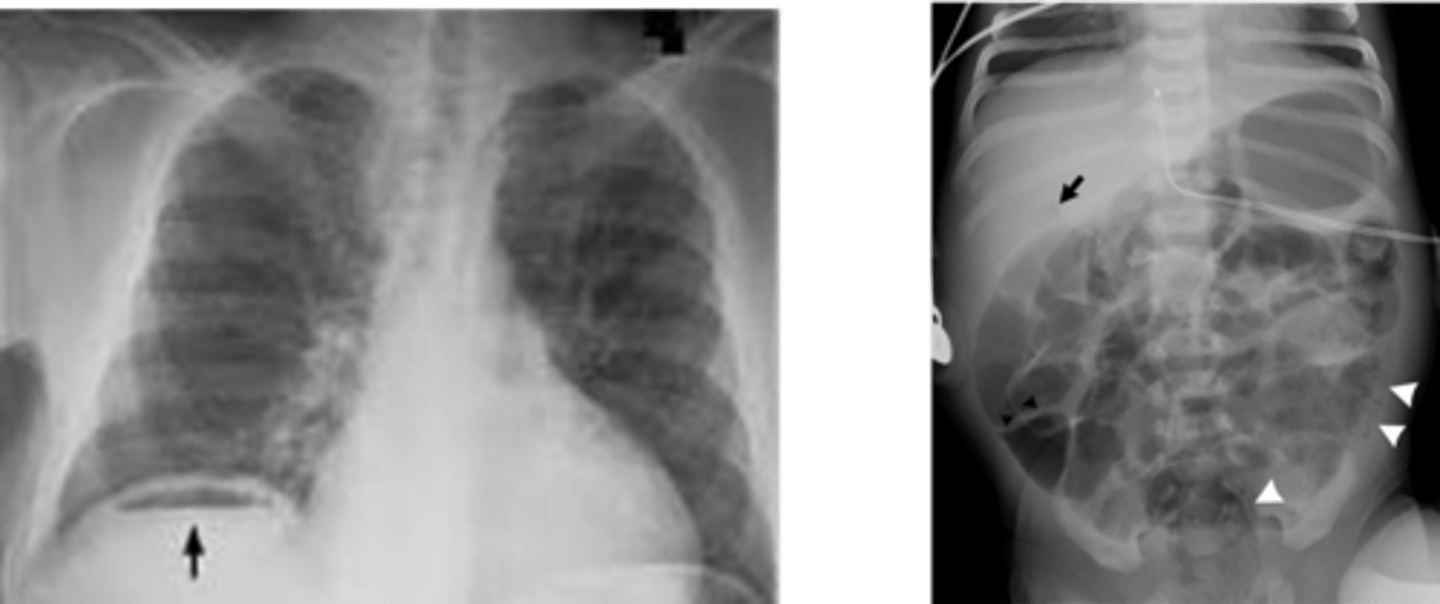

Air fluid levels due to small bowel obstruction (SBO)

Intramural air because of necrotizing enterocolitis (NEC)

dilated loops of bowel air fluid levels

dilated loops of bowel

string of pearls sign- diagnostic of mechanical obstruction

stretch sign- small pockets of gas trapped bn valvulae conniventes within fluid filled bowel